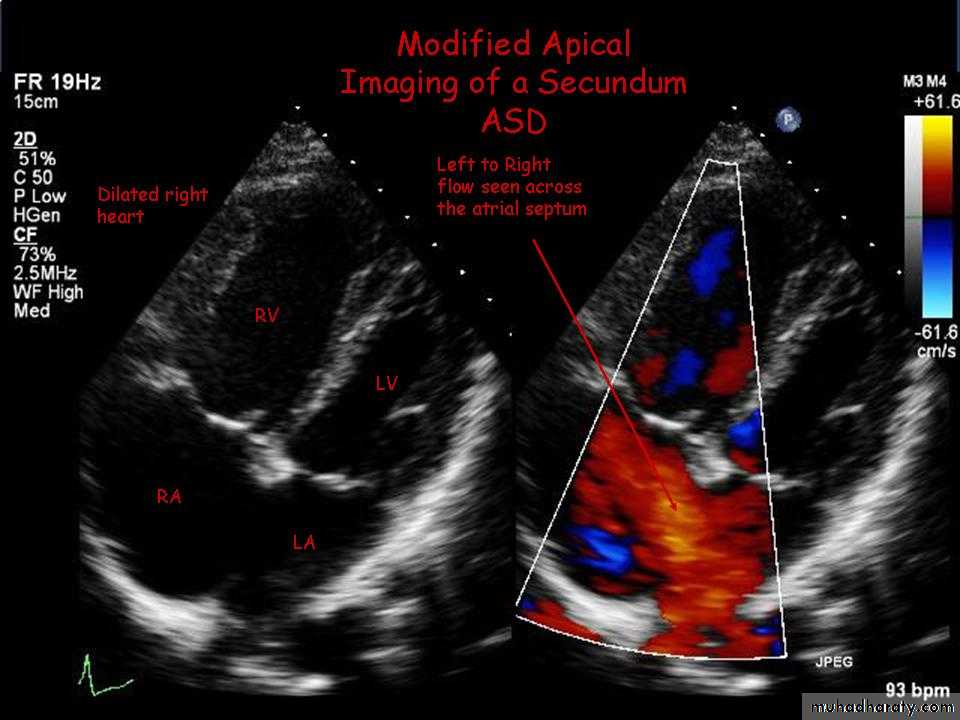

• Echo:• Trans-thoracic & trans-esophageal echocardiography is essential for Dx.

Large Secundum ASD